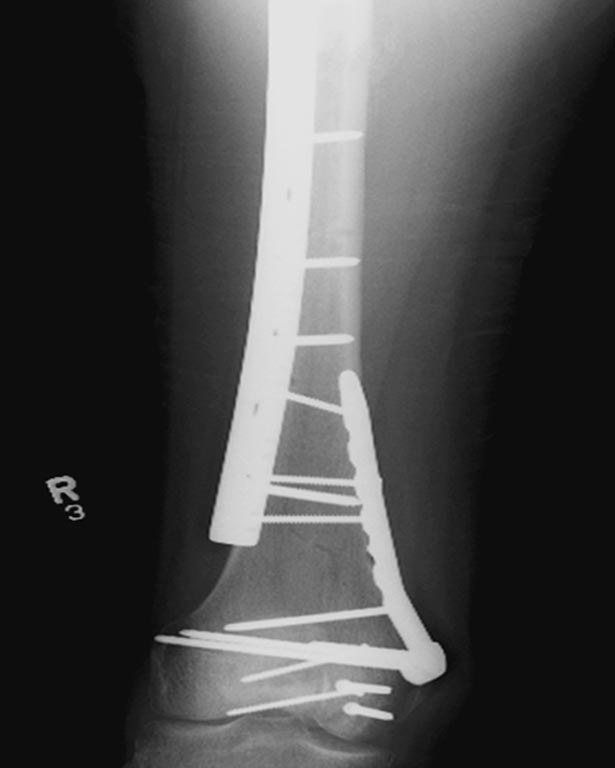

На 25 день с момента травмы операция на Jackson table с боковым обширным

доступом. Удаление стержней с местной обработкой. В тазобедренном

суставе удаление головки, на дне вертлужной впадины полная отслойка

хряща. Вертлужный компонент с одним винтом и короткая ножка -  Fitmore

Выписана. Нагрузку разрешили на левой стороне, а полная в 3 мес.  Здесь

снимки при амбулаторном наблюдении​: послеоперационно, 2 мес, 3 мес и 6

мес. Нагрузка полная, отсутствует хромота, и нет жалоб.